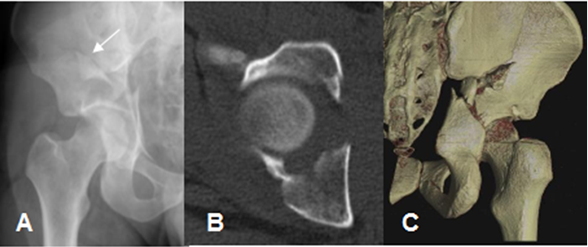

Fig 44. Trauma de pelvis. Compresión vertical.

A: Rx AP. Fractura del reborde interno y superior del acetábulo, que se extiende al hueso iliaco.

B: TAC axial. Fractura acetabular del reborde medial y posterior.

C: TAC reconstrucción 3D, donde se confirman los hallazgos.